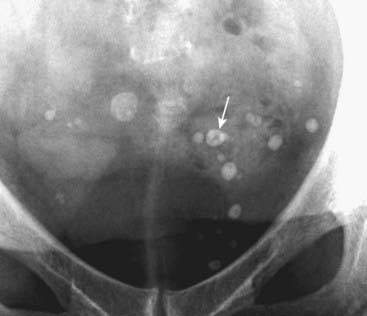

Figure 13-18 Phleboliths.

Phleboliths are small, rounded calcifications that represent calcified venous thrombi that occur with increasing age, most often in the pelvic veins of women. They classically have a lucent center (solid white arrow). In the pelvic veins, they are considered incidental and nonpathologic calcifications, but they can be confused with ureteral calculi.